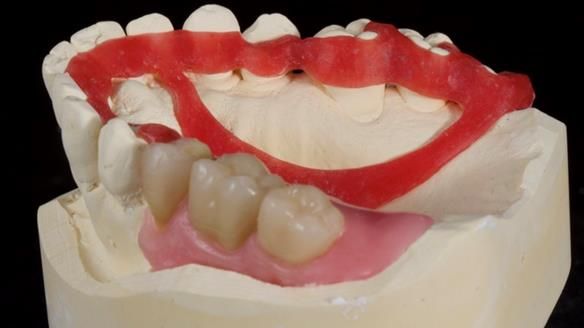

Welcome to Newsletter 64. I'll walk you through the process of providing a Mk 2 metal-based partial denture (RPD), for Ian a retired Veterinary Surgeon aged 78. The RPD was made at an increased vertical dimension and acted as an occlusal stabilisation splint - reducing the wear and bite force on the remaining natural teeth.